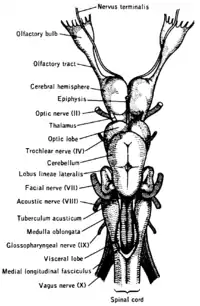

top; ventral bottom; lateral

The accessory nerve (XI) and hypoglossal nerve (XII) cannot be seen, as they are not always present in all vertebrates.

Cranial nerves are also present in other vertebrates. Other amniotes (non-amphibian tetrapods) have cranial nerves similar to those of humans. In anamniotes (fishes and amphibians), the accessory nerve (XI) and hypoglossal nerve (XII) do not exist, with the accessory nerve (XI) being an integral part of the vagus nerve (X); the hypoglossal nerve (XII) is represented by a variable number of spinal nerves emerging from vertebral segments fused into the occiput. These two nerves only became discrete nerves in the ancestors of amniotes.[28] The very small terminal nerve (nerve N or O) exists in humans but may not be functional. In other animals, it appears to be important to sexual receptivity based on perceptions of pheromones.[3][29]

The cranial nerves in the horse Ventral view of a sheep's brain. The exits of the various cranial nerves are marked with red.

Ventral view of a sheep's brain. The exits of the various cranial nerves are marked with red.